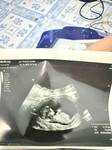

แม่เจอน่องตอนกี่วีคค่ะ ทางนี้ไปซาววันนี้เจอเเค่ถุงค่ะ ประจำเดือนล่าสุด 13 ก.ค นับได้ 7 w4dไปอัลตราซาวได้ 6w3 d

บ้านนี้เจอตอน6วีค3วันค่ะ อายุครรภ์บางทีอาจจะมีคาดเคลื่อนบ้างให้ยึดตามอายุครรภ์ที่ซาวได้เลย อาจจะต้องรออีกสัก2-3วีคจะได้เจอตัวน้องค่ะแม่

ทางนี้นับวันนี้ 7 วีค 6 วัน ตอนไปอัลตราซาว 6 วีค 3 วัน เจอถุงเหมือนกันหมอนัดอีกที 19 ค่ะ หมออนันตชัย

เพิ่งไปซาวมาวันนี้หมอว่า6w3d เจอหัวใจน้องแล้วค่ะ

เจอตอน 7 w2d ค่ะ ถ้านับตามแอพ 7w 6 d ค่ะ